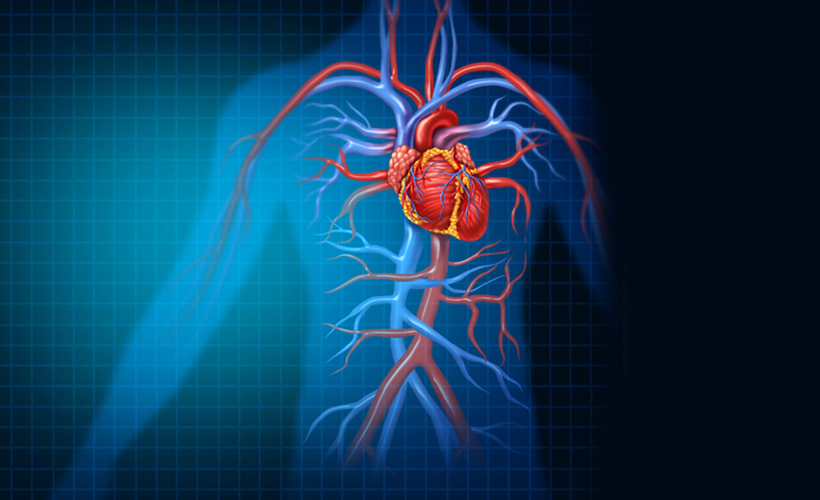

Fındıkzade Medipol Üniversitesi Hastanesi Kardiyoloji Bölümünden Uzm. Dr. Kemal Kunovac, “Lupus hastalığı cilt, eklem, böbrek, beyin, kalp ve damarlar gibi çeşitli organlara zarar veren otoimmün bir hastalıktır. Otoimmün hastalıkta bağışıklık sistemi kendi sağlıklı hücrelerine zarar verir. Normal koşularda bağışıklık sistemi vücudu mikroplara ve alerji yapan maddelerden koruyan bir sistemdir. Ancak bazen bağışıklık sistemi kendi dokularını tanıma özelliği bozulur ve onlara zarar veren maddeler olarak görmeye başlar. Bu durumda otoantikor denilen savunma maddesini üreterek sağlıklı dokulara saldırıp çeşitli bölgelerinde iltihaba yol açar” diye konuştu.

Lupus hastalığının daha çok kadınlarda görüldüğünü belirten Dr. Kunovac, “Dünya ortalamasında 100 bin kişi içerisinde 40-50 kişide görülür. Daha çok 15-45 yaşlarında görülür ve hastaların yüzde 90'ı kadınlardır. Tanısı önce özel kan testleri ile konulur ve sonra daha ayrıntılı tahlillerde doğrulanır. Deri döküntüleri, ağrılı ve şişmiş eklemler en sık gören bulgulardır. Ancak Lupus tüm organları etkileyebilir. Kalp ve damarların bu hastalıktan etkilenmeleri görülür. Perikardit (kalp zarı iltihabı) en sık görülen kalp tutulumudur. Göğüs ağrısı ve nefes darlığı belirtileri ile başlar, daha sonra ateş ve taşikardi (kalp hızında artış) gelişir. Tanısı EKO kardiyografi ile konulur, kalp çevresindeki sıvı miktarı görülür” ifadelerini kullandı.

Endokardit yani kalp kapakçıların iltihabının da Lupus hastalarında sık görüldüğüne dikkati çeken Dr. Kunavaç, sözlerine şöyle devam etti:

“Genellikle kalp kapakçıların ucunda yerleşen iltihabı EKO kardiyografi cihazı ile görülür. Koroner arter hastalığı Lupuslu hastalarda atrteroskleroz yani damar sertliği, damar duvarı iltihabı ya da tromboz dediğimiz damar içi pıhtılaşması olarak görülebilir. Efora bağlı göğüs ortasında vuran ağrı veya yanma belirtileri ile meydana çıkar. Kalp krizlerine ve ani ölümlere yol açabilir. Koroner anjiyografi ile tespit edilir.”

Dr. Kunovac, “Miyokardit dediğimiz kalp kası iltihabı ciddi nefes darlığı, taşikardi ve aritmi şikayetleri ile ortaya çıkar. Bu bulgular kalp yetmezliğini işaret eder. Kalp boşluklarının genişlemesi ve kalp kaslarının kasılma gücünün zayıflamasının nedeni olan Lupus hastalığının bu tutulumu EKO kardiyografi ile tespit edilir. Lupus hastalarının hastalıkları konusunda eğitilmesi şarttır. Bu hastalar sigara içmemeli, alkolden ve aşırı tuz tüketiminden uzak durmalıdır. Lupuslu hastalar, günlük yaşamlarında normalden daha fazla dinlenmeli, stresten ve sıkıntılı durumlardan korunmalıdır. Hastalık süresi konusunda bilgilendirilmeli, verilen tedavisi uygulanmalı ve periyodik olarak yapılan kontrol muayeneleri ihmal edilmemelidir” ifadelerini kullandı.